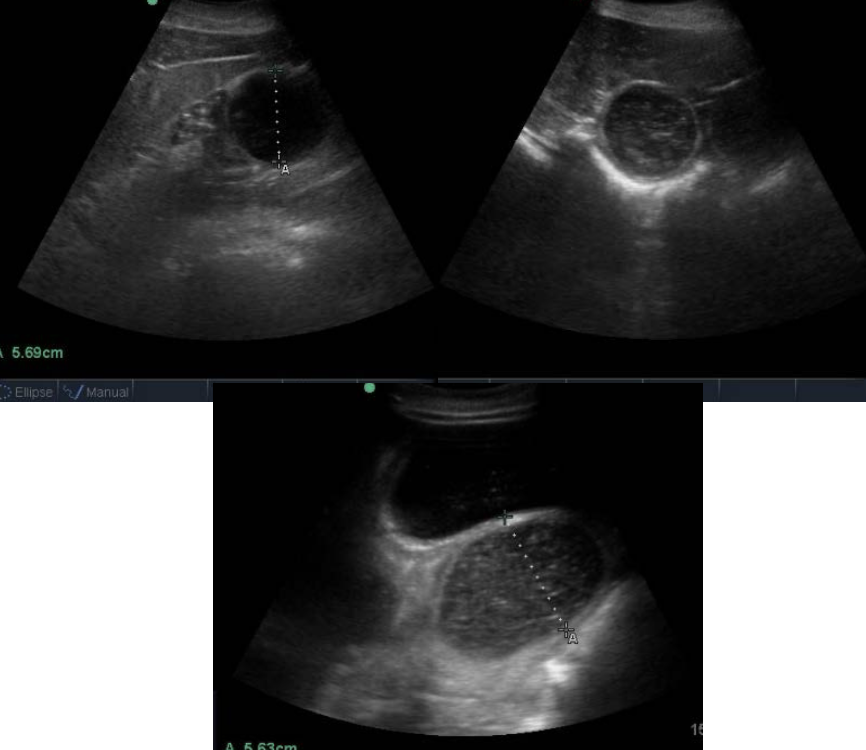

what is intussusception?

telescoping of the intestine: one segment (intussusceptum) passes inside an adjacent segment (intussuscipiens)

causes venous occlusion (edema, engorgement, and thickening)

what is the most common site of intussusception?

ileocecal (ileum going into cecum)

how is intussusception diagnosed?

1. NGT: reflux

2. rectal: SI distention, mass may be palpated at cecal base

3. US: SI distention and target lesion

4. abd. fluid: variable results since strangulating bowel is contained in adjacent bowel